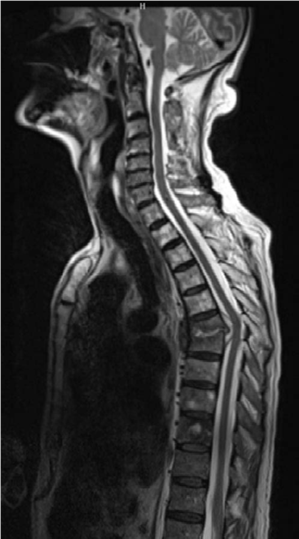

Spine structured oral questions5: Lumbar spinal stenosis and cervical myelopathy EXAMINER : A 70-year-old lad…